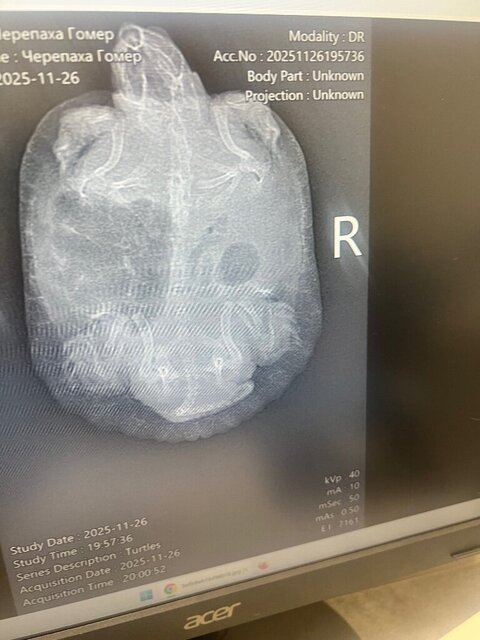

2. Недели 1,5 назад были на приеме сказали 7-14 дней рингера колоть, также сделали рентген обратились в клинику так как веки опухли и не открывает Уже 8 дней колим и капаем капли изменений нет, может подскажите Рентген прилагаю и назначения врача

20. @moth Нашла в городе одну клинику, которая всё-таки согласилась сделать нам снимки. Забор и анализ крови из вены нам пока нигде сделать не согласились. Сделала ей первый укол кальция, Элеовит должен через 3-4 дня в Витебск прийти.

28. @AlisaB Борглюконат кальция 0.45мл под кожу задней лапы или в мышцу попы через день, курс 5 инъекций вот тут как делать уколы https://cherepahi.ru/soderzhanie/zdorovie/kak-delat-ukoly-cherepakhe/ по-хорошему нужно сделать рентген, чтобы проверить нет ли в лёгких воспаления. Если за 3-4 дня лучше не станет - поищите вет препарат с действующим веществом Энрофлоксацин, правда не знаю можно ли в Беларуси купить вет антибиотик без рецепта. Белое это соли мочевой кислоты. Для водных это не свойственно, но сказать плохо это или просто разовое явление можно только сделав анализ крови.